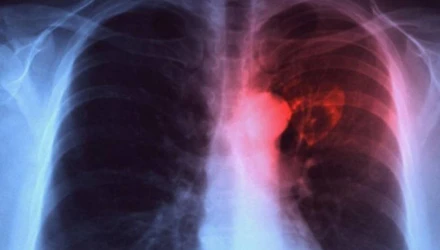

Φυματίωση: «Συναγερμός» από τον ΠΟΥ, η νόσος επιστρέφει

Τον κώδωνα του κινδύνου κρούει ο Παγκόσμιος Οργανισμός Υγείας για την έξαρση της φυματίωσης λόγω της πανδημίας του κορωνοϊού και των περιορισμών της, που μείωσαν τους ελέγχους και την πρόσβαση στην περίθαλψη, μιλώντας για 1,6 εκατομμύριο θανάτους παγκοσμίως το 2021.